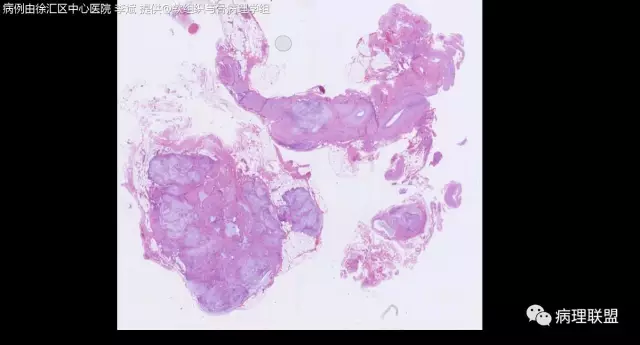

女,64岁,右腕部肿块,灰白不整形1*1*0.8cm(病例由徐汇区中心医院 李斌提供,致谢!)

神经鞘粘液瘤。

富于细胞神经鞘粘液瘤,s100阴。

关节旁粘液瘤,肿瘤中间明显有腱鞘囊肿结构,又发生在关节处!强烈提示为关节旁粘液瘤,部分病例可以呈分叶结构!平时多加观察腱鞘囊肿囊壁常可见粘液变性!范围一广就成粘液瘤样。